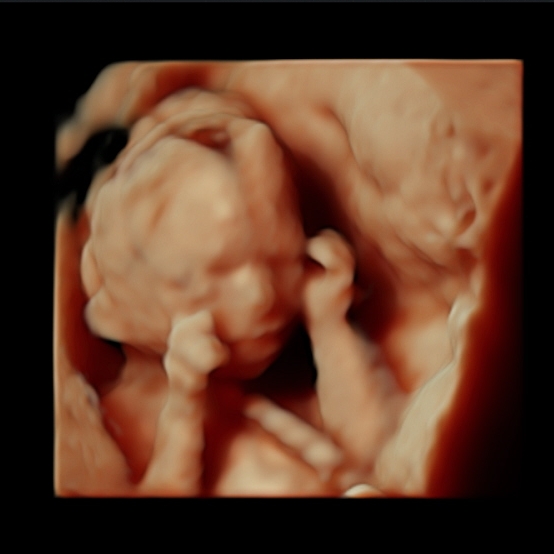

We have the latest ultrasound technology (HD Live) available. We provide you with the clearest 4d ultrasound images and nothing is left to the imagination, here is a reality, you will see your baby's movements in real time. We have some of our babies' images in our gallery so you might look according to your gestational age and get an idea of how you will see your baby. Please scroll down this page for more samples of our before and after baby pictures. They will give you a better idea of what are you getting when you book a 3D/4D/HD Live ultrasound session with Preggoland. We cannot wait to enjoy this unforgettable experience with you!

18 to 25 Weeks

Graphical explanation of how the babies are looking according to the gestational age. All 2D, 4D & HD Live images featured here have been taken by Preggoland. Please use them as a reference for your booking, from 12 weeks of pregnancy to 18/19 you can get beautiful full-body pictures & videos, your tiny human is growing fast. Don’t miss the opportunity to watch your baby’s development.